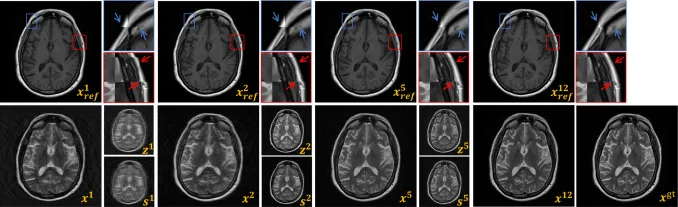

图14. 阶段t的中间结果可视化:地面真实xgt,重建图像xt,扭曲参考图像T(xref,Ï•t)表示为xreft,跨模态先验zt,以及模态内先验st。